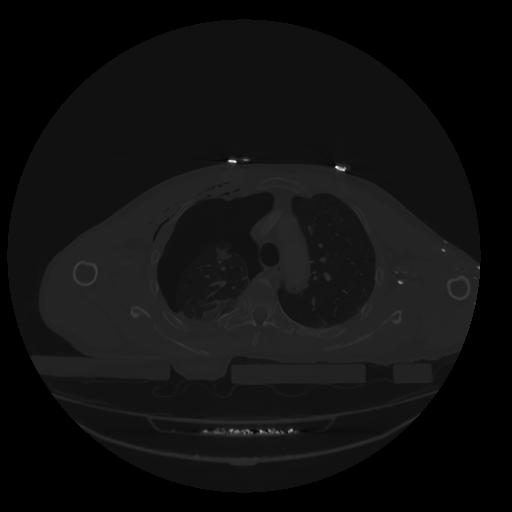

28 CUERPO,CE,Vol,2.0,CUERPO,,